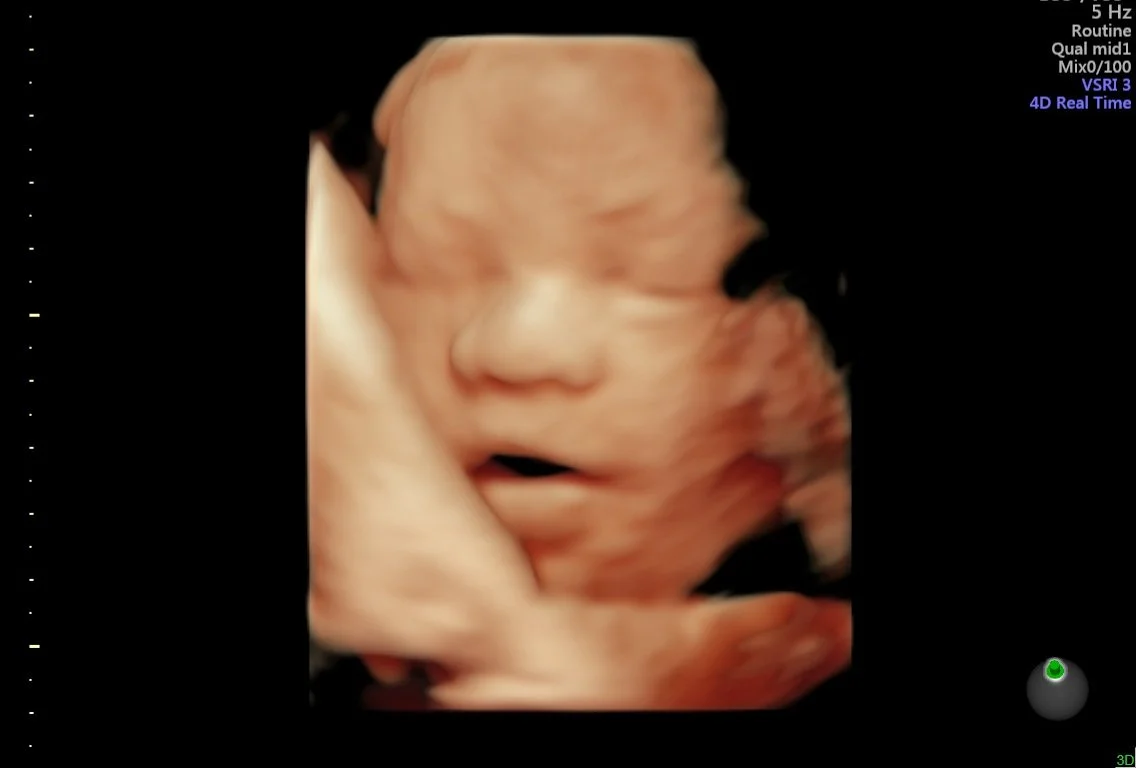

Our state of the art technology allows us to see your baby in a whole different way! With HD Live imaging, we can watch your baby wiggle, smile and yawn all in real time!